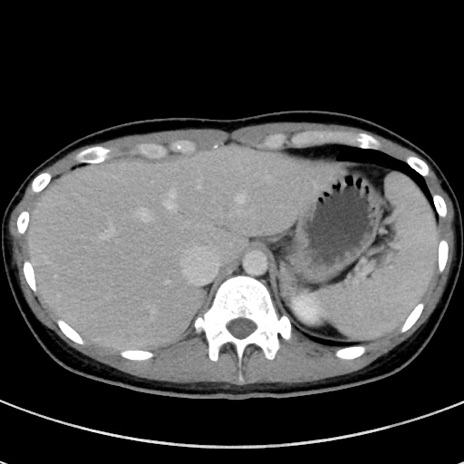

症例17(横断像)

【症例】20歳代女性

【主訴】嘔吐、下腹部痛

【現病歴】昨日夕食後に嘔吐し下腹部痛が出現。本日になっても嘔吐持続し改善しないため来院。

【身体所見】意識清明、BT 37.2℃、BP 108/67mmHg、腹部:平坦、やや硬、下腹部正中から右にかけて圧痛あり、反跳痛軽度あり、tapping pain(+)。

【データ】WBC 13600、CRP 14.94